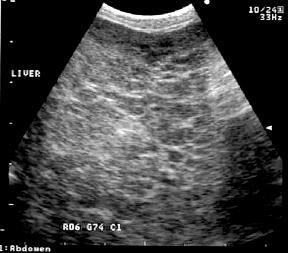

HepatocutaneousSyndrome

•Raremetabolicdiseaseaffectingprimarilyolder dogs

•Mostcommoncauseindogsisanunderlying hepatopathy,lesscommonlyaglucagonoma

•Hepatopathyisfrequentlyidiopathic, occasionallyassociatedwithphenobarbital administration

SecondaryDiagnostics

•Biopsy

•Classic“Red,WhiteandBlue”patternof hepatocutaneoussyndrome

•Serumaminoacids

•AbdominalUltrasound

•“SwissCheese”liver(mayormay notbepresent)

•Mayalternativelydetect glucagonomasorother pancreaticorhepatictumors